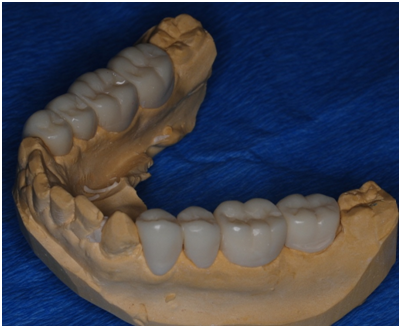

Study casts were poured and mounted according to registered intra occlusal records on which an occlusal splint was made first with a thickness of 1mm; the patient was instructed to wear it for 3 weeks. When the splint thickness was increased into 2mm, the patient complained after 1 week wearing the splint. Accordingly, the thickness of the splint was reduced to 1.5mm. After wearing the splint for two more weeks with no complaints, the splint was then used in the lab to help to construct temporary crowns; the procedure included dividing the splint at the midline to help to mount the cast with the required VDO. One side of the splint was left in place to be used as a guide for the required VD while constructing temporary crowns for the other hand. At the clinic posterior teeth were prepared; first, temporary crowns were constructed following the wax up made in the lab to raise the VDO. The anterior teeth were then prepared and temporary crowns were placed (Figure 8). The patient complained of pain in the lower right premolar area, upon examination tooth # 28 needed root canal treatment.

Figure 8 Study cast upper.

Figure 9 Study cast lower.